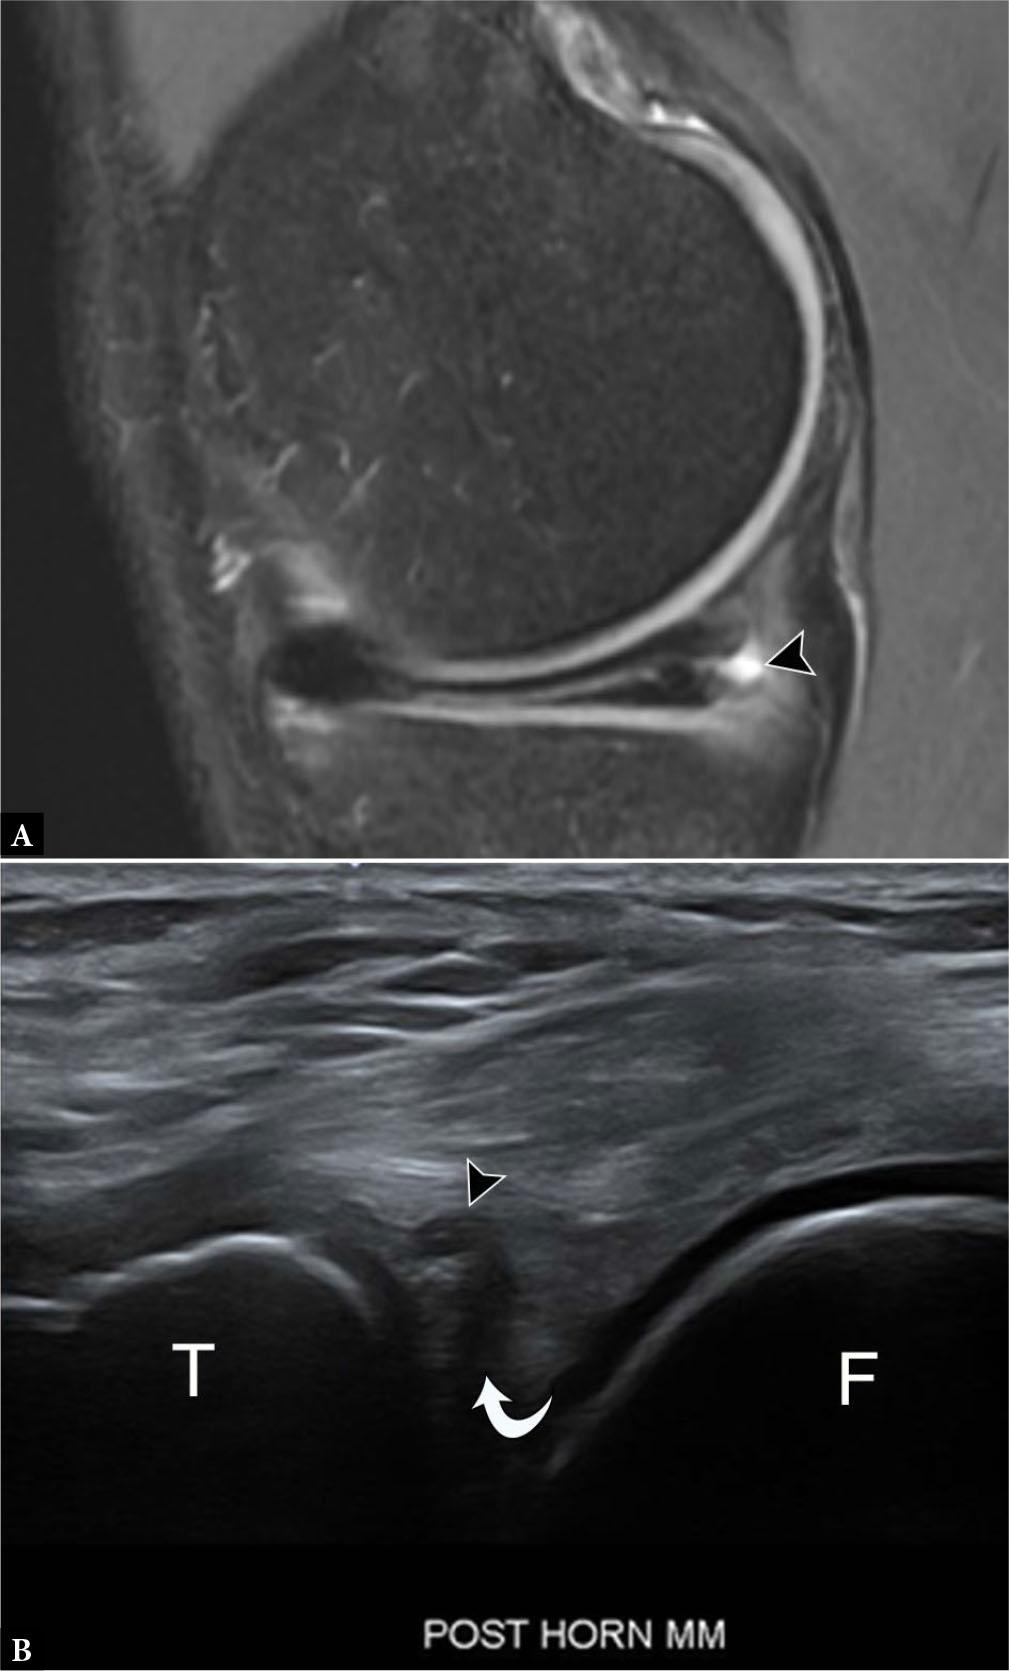

MRI is regarded as the imaging gold standard for meniscal evaluation, and US is not reliable as a sole imaging modality(2,4). A meta-analysis of 27 studies reveals MRI sensitivity and specificity of 93% and 88% for medial meniscal tears, and 79% and 96% for lateral meniscal tears, respectively(41). On both T1-weighted and T2-weighted imaging, the normal fibrocartilaginous menisci are hypointense triangular structures. Meniscal degeneration is defined as increased linear or globular intrasubstance fluid-signal not disrupting a meniscal surface(42). Fluid-signal intensity extending to the meniscal articular surfaces on two contiguous slices is diagnostic of a tear (Fig. 12 A). Additionally, MRI can characterize the different types of meniscal tears and the presence or absence of displaced meniscal tissue, which is vital to the orthopedic surgeon in determining surgical versus non-surgical treatment.

Fig. 12.

37-year-old male with horizontal meniscal tear and smallparameniscal cyst. A. Sagittal proton-density-weighted fat-suppressed MR image demonstrates horizontal tear extendingfrom the free edge of the medial meniscus to the periphery, with associated parameniscal cyst (arrowhead). B. Longitudinal grayscale US image of the posterior knee shows a horizontally oriented, hypoechoic cleft, consistent with a tear (curved arrow), in the echogenic, triangular posterior meniscus with a small, contiguous parameniscal cyst (arrowhead). T – tibia, F – femur

On US, only the peripheral portions of the menisci are visualized as triangular hyperechoic structures. Meniscal degeneration is typically visualized as tissue heterogeneity, either with or without extrusion or fragmentation, while a true meniscal tear will appear as hypo- or anechoic linear defects extending to the periphery of the meniscus (Fig. 12 B)(2). Tears deep to the visible meniscal periphery are difficult to visualize, with a reported sensitivity for medial and lateral meniscal tear as low as 0% and 8%, respectively(4). While the overall sensitivity and specificity of detecting all meniscal tears on US is 85% and 86%, respectively, US is highly accurate at diagnosing parameniscal cysts, which is a secondary sign of an underlying meniscal tear(2,43).